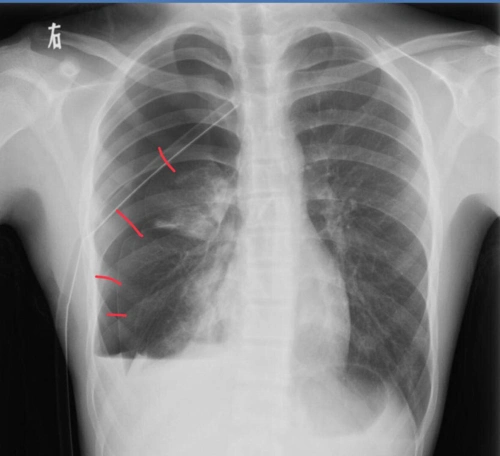

胸部ct 薄层ct可以发现肺大泡,另外一些隐匿部位的气胸,胸片不能发现